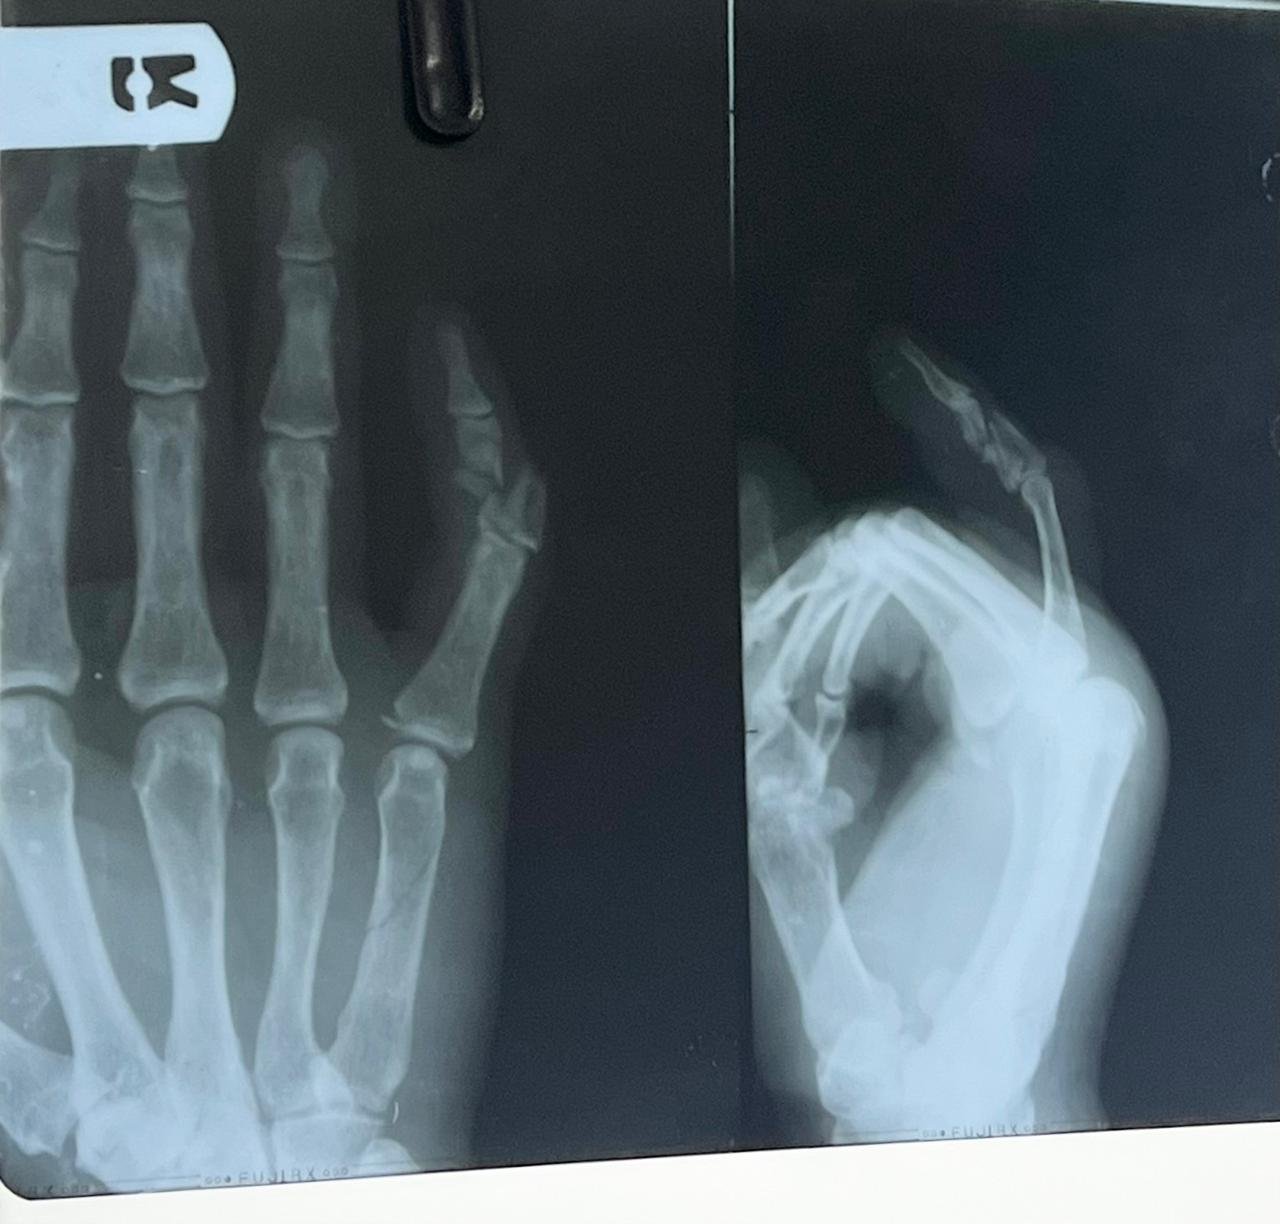

Clinic Exterior & Reception | Elbow dislocation &

operative treatment